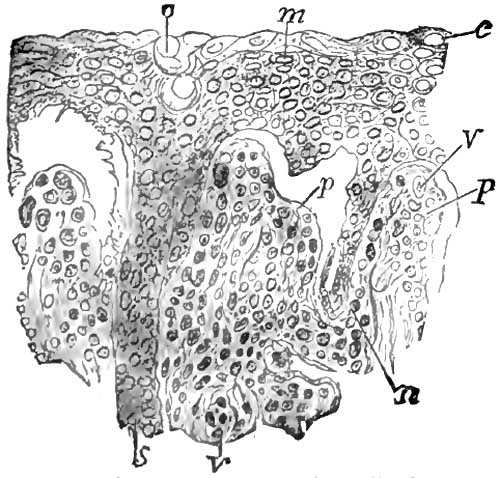

| 7. | SECTION OF RETE MUCOSUM AND PAPILLÆ FROM SAME CASE OF PEMPHIGUS AS FIG. 6 |

| 8. | SECTION OF AN OLD GUMMA OF THE LIVER |